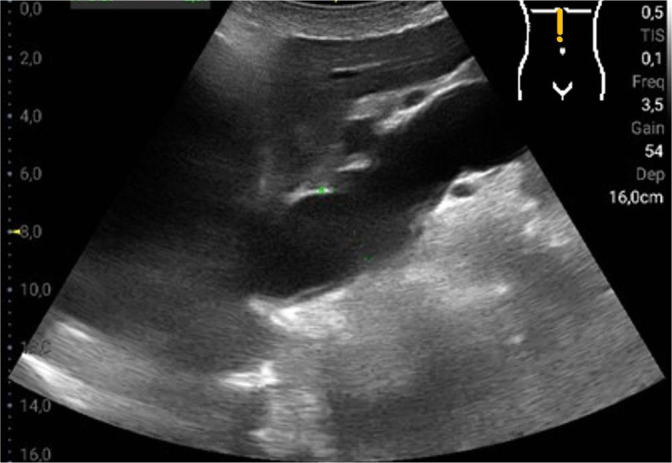

Results: The most common pathological findings were renal cysts in 34/120 (28.3%), left-sided or right-sided pleural effusions in 33/120 (27.5%) and 29/120 (24.2%) patients, respectively, dilatation of the vena cava in 24/120 (20.0%), and urinary retention in 14/120 (11.7%) patients. In 13/120 (10.8%) patients, the sonographic examination resulted in a diagnostic consequence, while in 38/120 (31.7%) patients in a therapeutic consequence. Among the false-negative findings using the hand-held ultrasound device, no finding was of therapeutic relevance. Four findings that were missed by the hand-held ultrasound device were diagnostically significant: two lesions of the kidney, one lesion of the liver, and one case of urinary stasis kidney.

Abstract Image